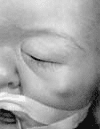

Las dificultades que encontramos siempre se debieron a la fijación anterior. En dos oportunidades hubo que retirar el sistema, ya que su porción anterior se encontraba desplazada causando sufrimiento cutáneo. (figura No. 8). En otro paciente se tuvo que interrumpir la distracción debido a una sobreinfección.

Figura. No 8 Fotografía que muestra desplazamiento anterior del pin del distractor y se proyecta a travez de la piel de este paciente con sindrome de Apert. Esto es indicación para retirar el distractor.